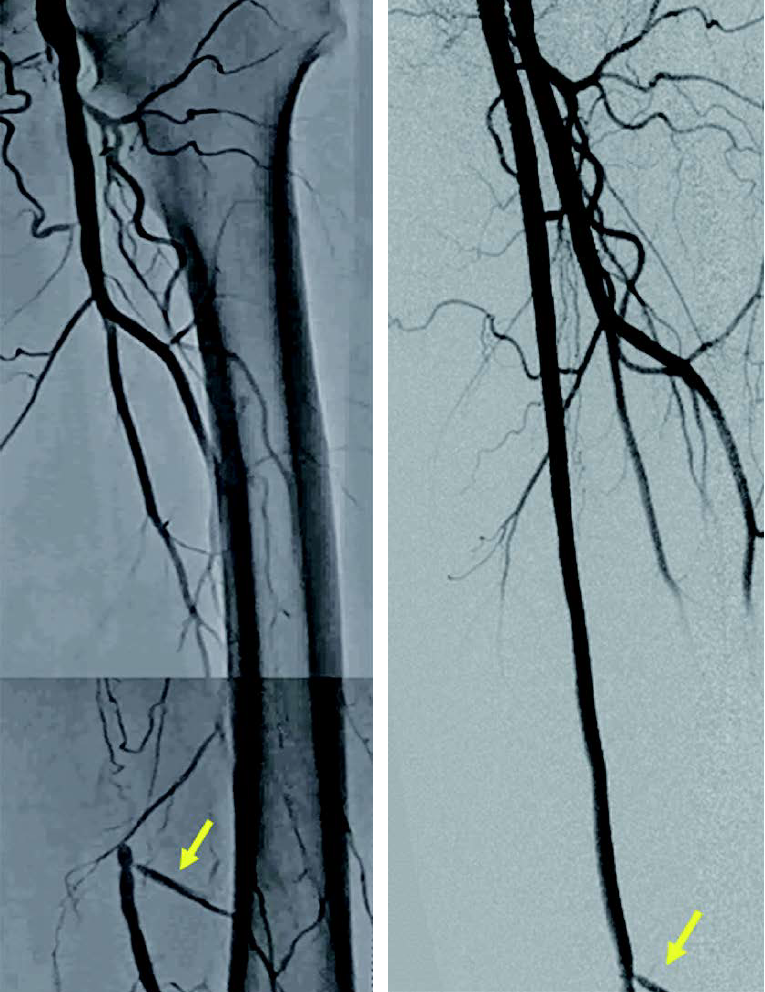

左浅大腿動脈閉塞(図1):右鼠径部を穿刺(6 Frシース)しcrossover後、順行性に0.014 inchマイクロカテーテルを使用して0.014 inchガイドワイヤー(先端荷重1 g→40 g)を進め貫通、IVUS catheterで真腔を捕らえていることを確認。5.0 mm径バルーン(non-compliant balloon)で拡張後解離が生じ、末梢にバイアバーン® ステントグラフト5.0 × 150 mm、中枢に6.0 × 150 mmの2本を留置。病変の末梢には発達した1本の側副血行路を伴い、側副血行路の中枢側に健常部位があったため、側副血行路をjailせずバイアバーン® ステントグラフトを留置。5.0 mm径と6.0 mm径バルーン(non-compliant balloon)で後拡張して終了。(図2)